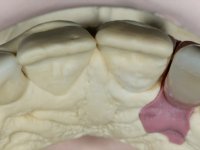

An impression was made on the implant with open tray technique using soft and regular consistency putty. At the laboratory, after confection of the work model, a diagnostic waxing was performed, which sought to find an aesthetic compromise solution. In this sense, a temporary workpiece screwed onto the implant was used to simulate the difficulties we would have with screwing the definitive work. This study abutment consisted of wax to reproduce soft and hard tissues, seeking to anticipate the use of ceramics of gingival and coronary shade. Also, part of the interproximal papillae corresponding to the distal portion of the 2.1 tooth and the mesial tooth of the tooth 2.3 were also waxed, anticipating the use of composite resin “chips” with gingival tonality. Finally, a veneer was waxed to correct the microdontia of the tooth 1.2. In this waxing, the vestibular emergence of the orifice for access to the screw of the implant abutment was evident. Once this therapeutic option was accepted, the implant abutment in polymerized composite resin was prepared at the lab, as well as the papillary "chips", also in composite resin of gingival tonality. Tested in the mouth, the abutment was screwed and the "chips" bonded. The access hole of the screw was filled with composite resin. In subsequent consultation, a gingivectomy was performed on the cervical contour of teeth 1.3, 1.2 and 1.1 with the aim of correcting the asymmetry between the first and second quadrant. After the soft tissues were cicatrized, a dental bleaching was performed according to the patient’s aesthetic requirements. Final impression on the implant was made using the silicone open tray technique, taking care to individualize the transfer piece by copying the emergence profile of the patient’s provisional abutment. At the laboratory, the impression yielded a definitive working model, on which the abutment was waxed on a plastic insert. This process was carried out with the orientation of a wall of silicone based on diagnostic waxing. The wax made on the plastic part was placed in a special holder that allowed its scanning in a laboratory scanner. This scan by CAD process informed the design of an abutment in Zr. later materialized by a CAM process. The Zr. abutment was tested in the mouth, validating its clinical and imaging establishment. During this consultation, the choice of color was made by the ceramist, of both the coronary ceramics and the ceramic of gingival tonality to be used. Individualized color scales were used. At the laboratory, the coronary and gingival ceramics were placed on the implant abutment and later, on a working model with refractory gypsum, a veneer of feldspathic ceramic was made. This veneer was built on a surface specially designed for this purpose in the abutment. This surface tried to reproduce a dental preparation performed for the same effect. In the mouth the abutment was screwed with a torque of 35N, the access hole to the screw was filled with Teflon and later filled with composite resin. The veneer was bonded onto the implant abutment using the conventional bonding technique, with relative insulation. For economic reasons, the patient did not proceed to perform the veneer on tooth 1.2. Although a limited aesthetic compromise was expected from the outset, a result was achieved which satisfied the patient.